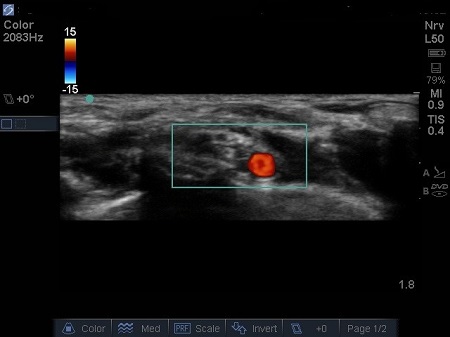

- The first structure to locate is the round pulsating hypoechoic subclavian artery (A), lying on top of the hyperechoic first rib (R). Use Doppler to assess for vessels. See Fig. 2.

Fig. 2. Bidirectional Doppler used here to highlight the subclavian artery.